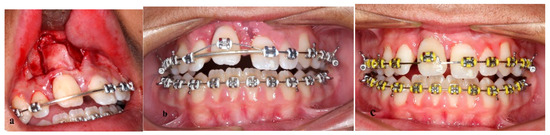

2. Materials and Methods